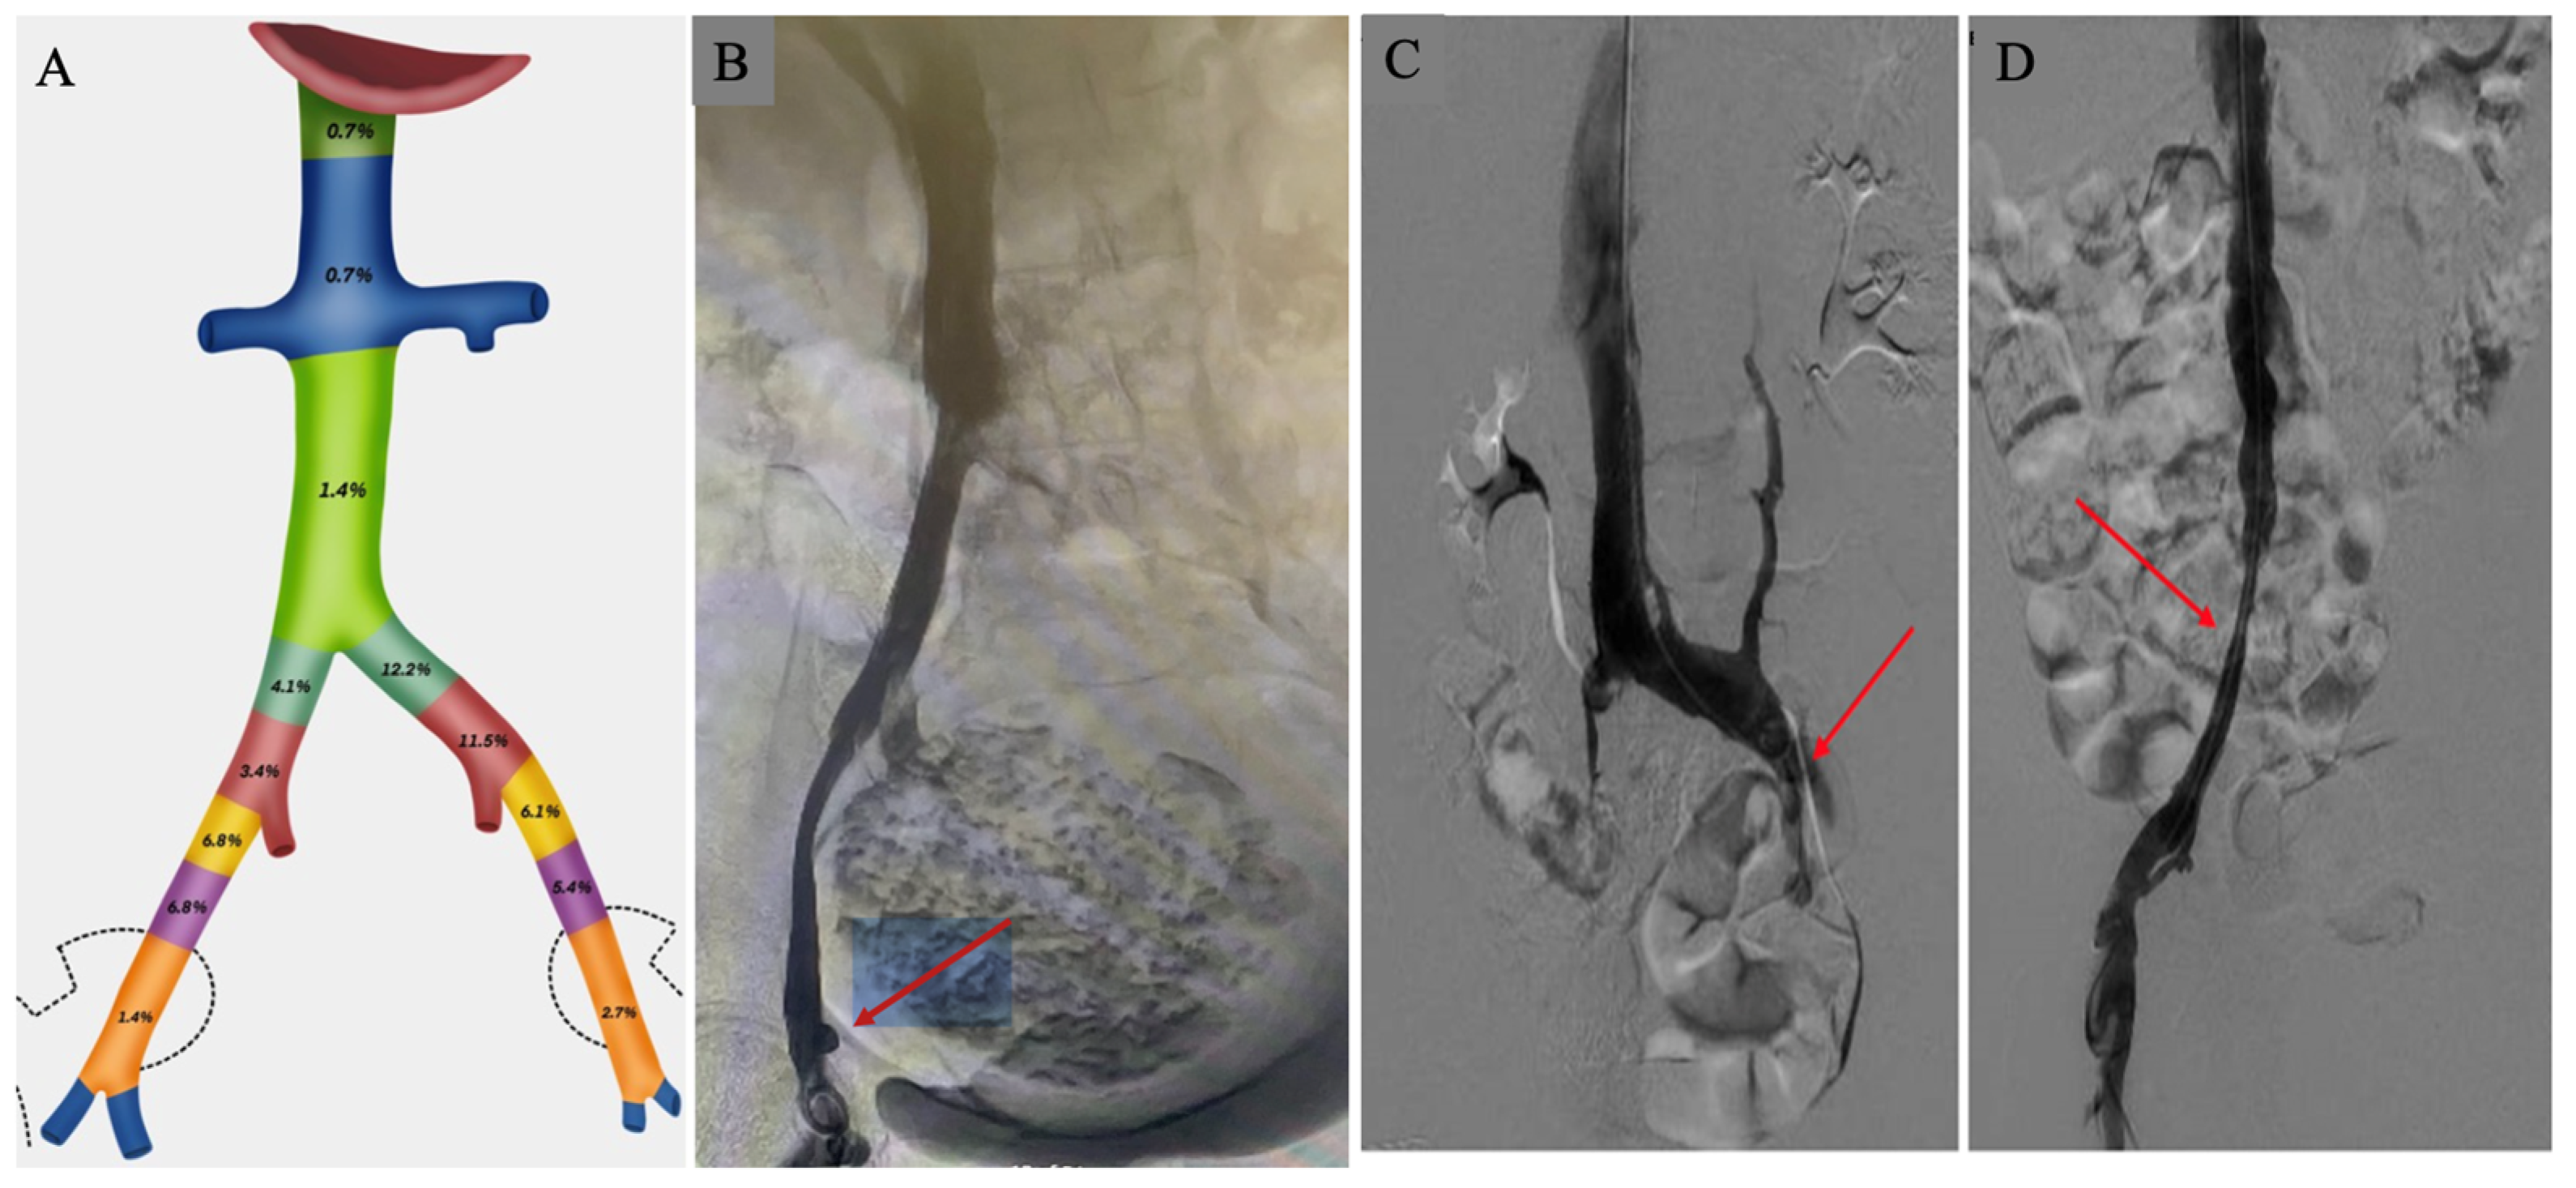

The most common anatomic level of PVO was the common iliac veins (31.2%), with the majority involving the left common iliac vein (23.7%). PVO involvement of the external iliac veins was similar between the right (15%) and left (14.2%) sides. Very few PVO occurred at the level of the inferior vena cava (2.8%) (Figure 2). There was no significant difference noted in right (40.0% in those with PVO vs. 37.3% in those without PVO, p = 0.742) or left (52.3% in those with PVO vs. 38.6% in those without PVO, p = 0.09) lower extremity post-thrombotic syndrome in the two groups. There were no differences in a history of inferior vena cava (IVC) filter placement (30.8% in those with PVO vs. 30.1% in those without PVO, p = 0.932) or IVC filter present at the time of the venogram (27.7% in those with PVO vs. 30.5% in those without PVO, p = 0.711). Of the 148 total patients, 17 (11.5%) underwent venous stent placement. All of these patients had PVO (p < 0.0001) (Table 2).

Figure 2. Pelvic vein obstruction. (A) Anatomic levels of PVO from inferior vena cava, common iliac veins, external iliac, and internal iliac veins. (B) Right external iliac vein compression by large uterine fibroid (arrow). (C) Left external iliac vein compression (arrow). (D) Right common iliac vein compression (arrow). PVO—pelvic vein obstruction.

In this study of CTEPH patients, the PVO by invasive venography was noted at the level of the common iliac veins in one-third of the patients. Importantly, the overwhelming majority of these involved the left common iliac vein, consistent with May-Thurner anatomy. The external iliac veins’ obstruction was equally common in 29.2%, albeit with equal distribution between the right and left sides. This suggests that while the mechanism of PVO in the common iliac veins can be largely attributable to a known congenital anatomic variant, there is a significant prevalence of external iliac vein PVO, which may be comprised of acquired (like uterine fibroids) or congenital abnormalities (like overlying arterial compression). Interestingly, while 30% of our patients had a history of an IVC filter, very few (2.8%) were noted to have obstruction or compression at the level of the IVC.